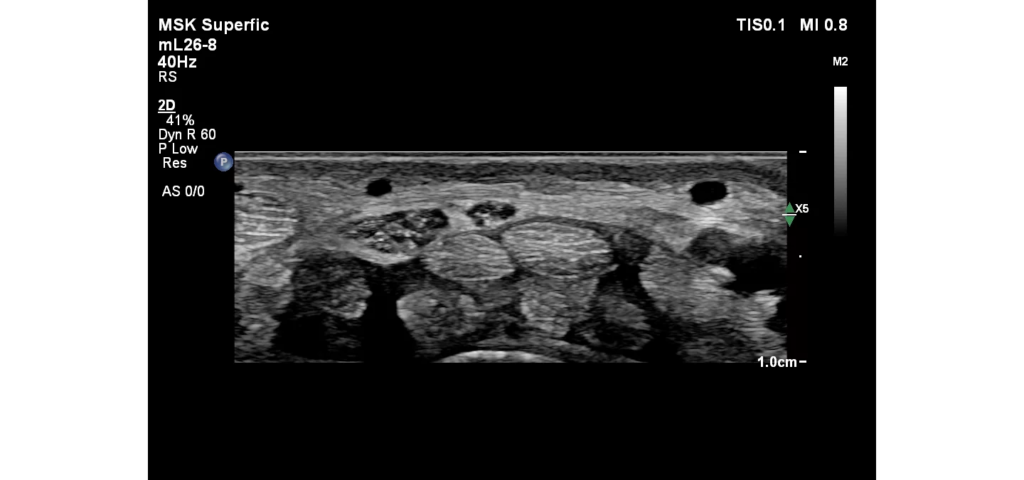

Philips EPIQ Elite ultrasound features an exceptional level of clinical performance, workflow, and advanced intelligence to meet the challenges of today’s most demanding practices. The EPIQ Elite platform brings ultimate solutions to ultrasound, with clinically tailored tools designed to elevate diagnostic confidence to new levels.